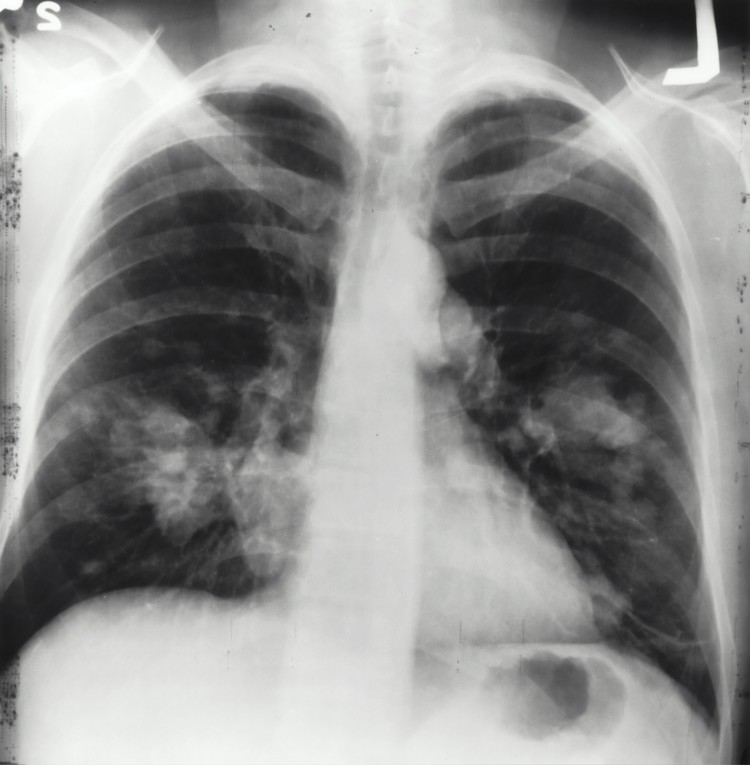

明日はCTとMRI

読影結果発表